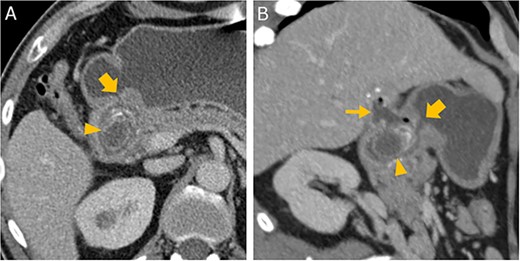

Abdominal CT in axial (A) and oblique parasagittal reconstruction (B); gallstone in the duodenal bulb (arrowhead

), pylorus (thick arrow

), chronically inflamed, and collapsed gall bladder with fistula to the duodenum (thin arrow

); image courtesy of Helmut Schöllnast, State Hospital Graz II, Austria.